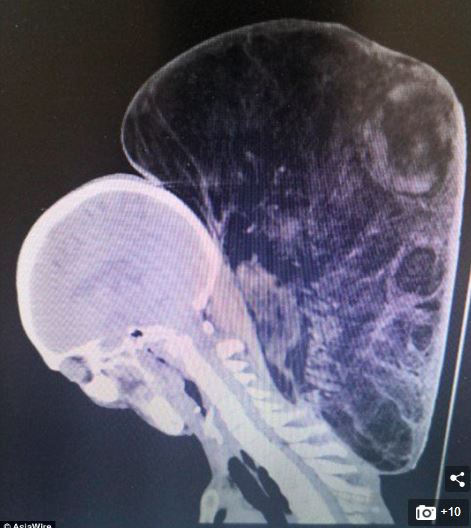

An X-ray shows the size of the growth, which was making it difficult for him to walk